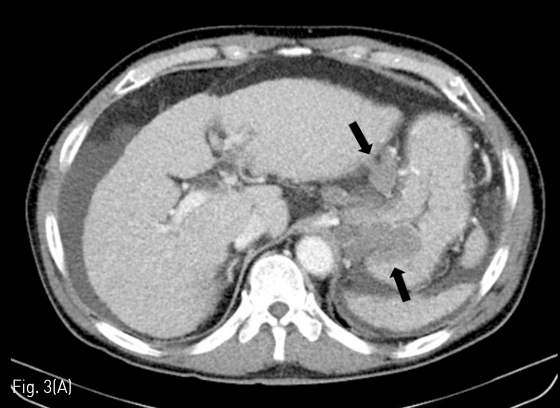

시술 전 시행한 dynamic liver CT에서 간경화 소견과 현저한 gastric varices, mesenteric-retroperitoneal varices가 관찰되었다 (Fig. 1A-C). Gastric varices는 gastro-renal shunt가, mesenteric-retroperitoneal varices는 meso-caval shunt가 각각의 경로로 생각되었다. Meso-caval shunt는 superior mesenteric vein (SMV)에서 right renal vein을 거쳐 inferior vena cava (IVC)로 유출되는 것으로 판단하였다. Esophageal varices도 보이긴 하였으나 경미한 정도였다.

Fig 1A

(A-C) Contrast-enhanced CT images obtained before PARTO show gastric varices (black arrows) and mesenteric-retroperitoneal varices (white arrows). Arrow head indicates dilated SMV. Curved arrow indicates the meso-caval shunt.